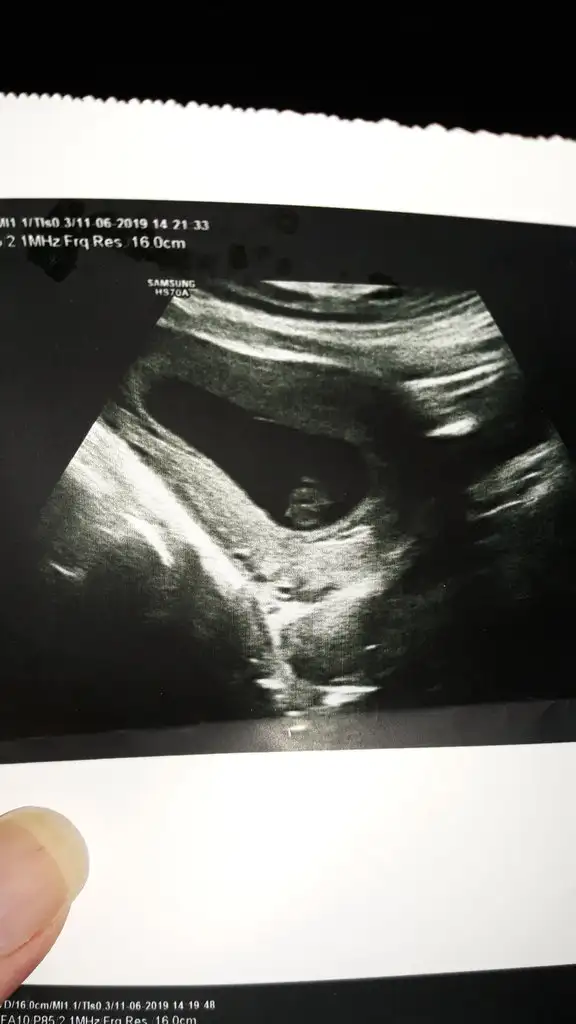

merhaba.. az önce ağrı ile birlikte kanama oldum.. doktora gittim..

usg bakıldı apdominal.. kalbi atıyor ama düşük tehlikesi varmış.. inşallah sağlıklıdır.. 😞

7+3